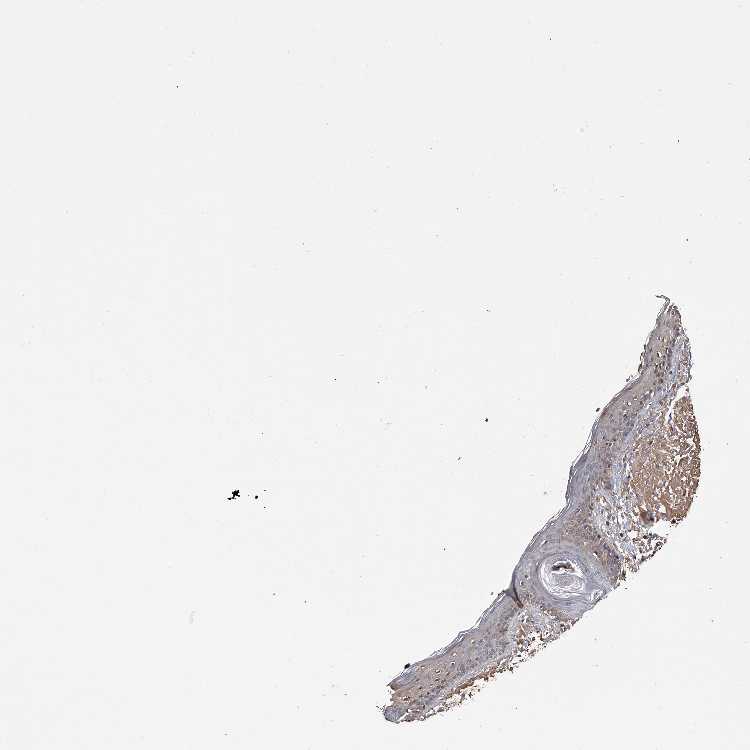

SKIN 1 - Antibody stainingi

Antibody staining in the annotated cell types in the current human tissue is reported as not detected, low, medium, or high, based on conventional immunohistochemistry profiling in selected tissues. This score is based on the combination of the staining intensity and fraction of stained cells.

Each image is clickable and will lead to virtual microscopy that enables deeper exploration of all samples and also displays staining intensity scores, fraction scores and subcellular localization as well as patient and tissue information for each sample.

Antibody HPA030190

Langerhans Not detected

Fibroblasts Medium

Keratinocytes Low

Melanocytes Medium